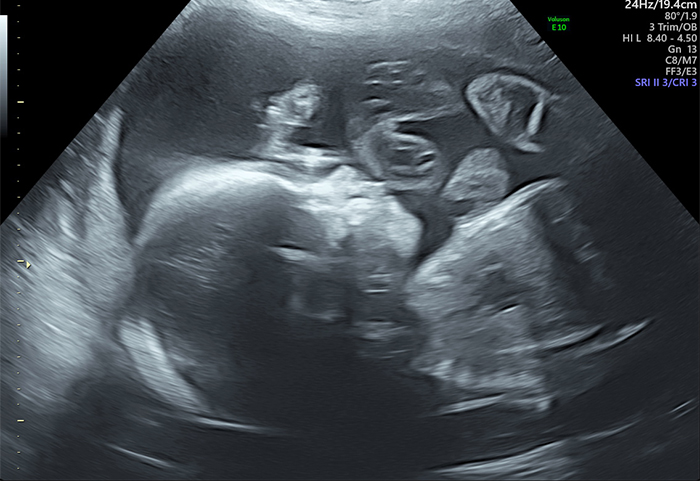

Anomaly Scans are detailed to assess each part of the baby’s anatomy to check fetal development and to exclude structural abnormalities performed between 20-24 weeks of pregnancy.

An anomaly scan, also known as the 20-week scan, takes a detailed look at your baby's development. The clinician carrying out the scan will check that your baby is developing normally and look at the placenta position.

• Assessment of your baby's anatomy which includes head & brain, face, spine, heart, lungs, bowel, abdominal wall, kidneys and bladder, stomach, arms/hands/fingers, legs/feet/toes

• Fetal growth/estimated weight, amniotic fluid, placental position and function, umbilical cord insertion, presentation (position of baby)